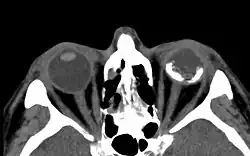

Phthisis bulbi (lateinisch für „Augapfelschrumpfung“) ist der medizinische Fachbegriff für die Schrumpfung und Atrophie des Augapfels, meist aufgrund rezidivierender Entzündungen des Auges oder schwerer Traumen.[1][2] Häufigster Pathomechanismus ist eine Atrophie des Ziliarkörpers. Das dort produzierte Kammerwasser versiegt, wodurch der Bulbus schrumpft und durch fehlende Ernährung atrophieren wichtige Strukturen des Auges. Eine Phthisis bulbi kann auch angeboren sein[3] oder sich frühzeitig dem Osteoporose-Pseudoglioma-Syndrom entwickeln.